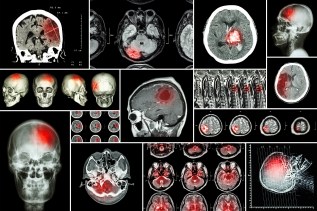

Researchers led by EPFL have found how lactate, a waste product of glucose metabolism can protect neurons from damage following acute trauma such as stroke or spinal cord injury. Read more